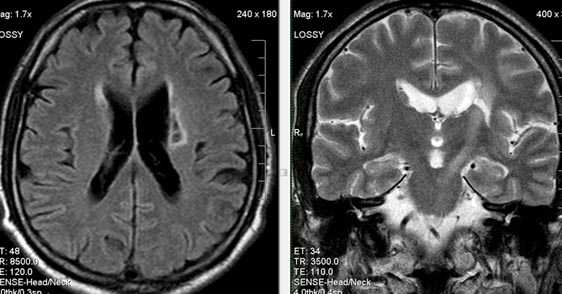

Характерным проявлением ДЭП на МР-томограммах является наличие множественных очагов глиоза.

В белом веществе левой лобной и обеих теменных долей, преимущественно субкортикально, выявлены множественные мелкие очаги хронической ишемии (большинство локализованных в бассейне правой средней мозговой артерии).

Проявлением хронической ишемии является также развитие выраженных дистрофических изменений белого вещества паравентрикулярной локализации - лейкоареоз.

Выраженные дистрофические изменения белого вещества паравентрикулярной локализации - лейкоареоз.

Сочетание мультифокальных очаговых изменений с диффузной кортикальной церебральной атрофией.